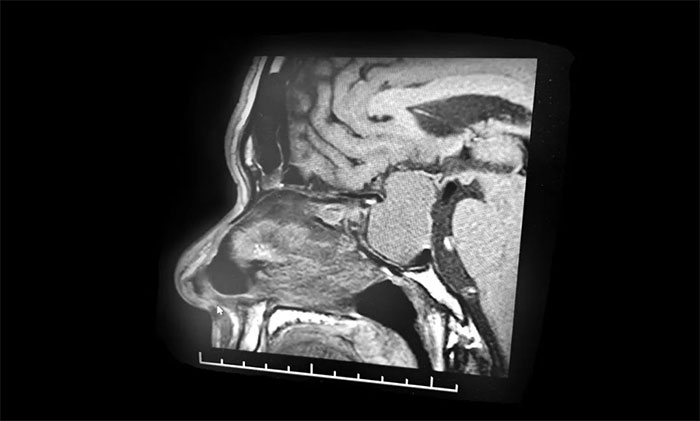

行鞍区磁共振增强提示:蝶鞍显著扩大,鞍区见一典型的“哑铃”状肿块,大小约40*43*24mm。病变向鞍上生长,凸入鞍上池,推移视交叉;向下生长,鞍底受压变薄、凹陷,蝶窦受压;右侧海绵窦可见包绕。

李士其教授、黎军主任、潘仁龙主任组成的专家团队通过详细了解病史和仔细阅片后,为患者认真分析了目前的病情及手术风险,并反复讨论、仔细评估。从影像学资料上看,肿瘤呈“哑铃”形,并且瘤体已经非常大了,属于巨大垂体瘤。瘤体占据鞍区,并向蝶窦和鞍上发展,侵袭右侧海绵窦,视神经、视交叉受压,所以需要马上进行手术切除,解除压迫,若任其发展,患者将来有失明的风险。

▲ 巨大垂体瘤,呈“哑铃”形